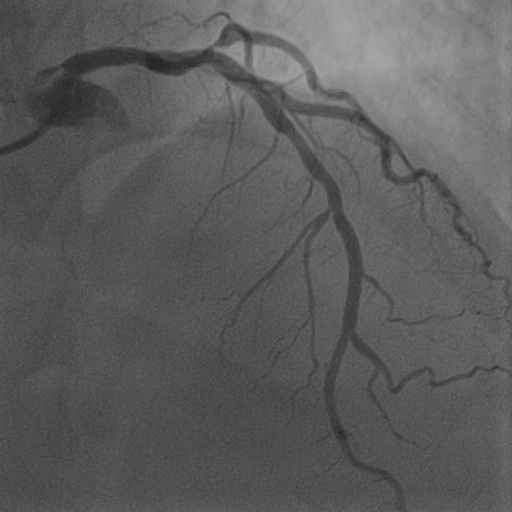

4.1 XACV Dataset

We collect 111 complete records of coronary artery X-ray videos, encompassing the injection, flow through the blood vessels around the heart, and dissipation of the contrast agent. Subsequently, we establish the XACV (X-ray Angiography Coronary Video) dataset. Each video consists of varying numbers of high-resolution coronary artery X-ray images. We invite experienced radiologists to annotate the vascular regions, focusing on one or two frames where the contrast agent is most prominent in each video. The XCAD dataset contains only a single image, and the CADICA video dataset does not provide corresponding ground truth. Therefore, in the following experiments, we conduct all the analyses on our collected XACV dataset and the corresponding GT for each sequence. In Figure 5, we show that compared to other publicly available datasets, XCAD [33] and CADICA [19], our dataset exhibits finer annotations in the vascular regions, providing an advantage for future related tasks. The development and use of our dataset have been approved by our institution’s IRB.